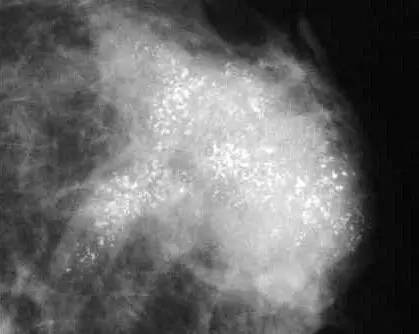

小娟的奶奶50多歲時患過乳腺癌,因此,小娟對乳腺的檢查也格外重視。某次體檢后,報告單上寫的是“左乳外上密集簇狀鈣化”。小娟由于看不懂,第二天就去醫院就診,醫生在鉬靶下行鉤針定位鈣化灶,手術切除鈣化灶。病理報告是“左乳導管原位癌”。

原位癌是比早期癌還要早的0期癌,一般沒有任何表現和不適,多數是常規體檢時鉬靶攝片才發現。